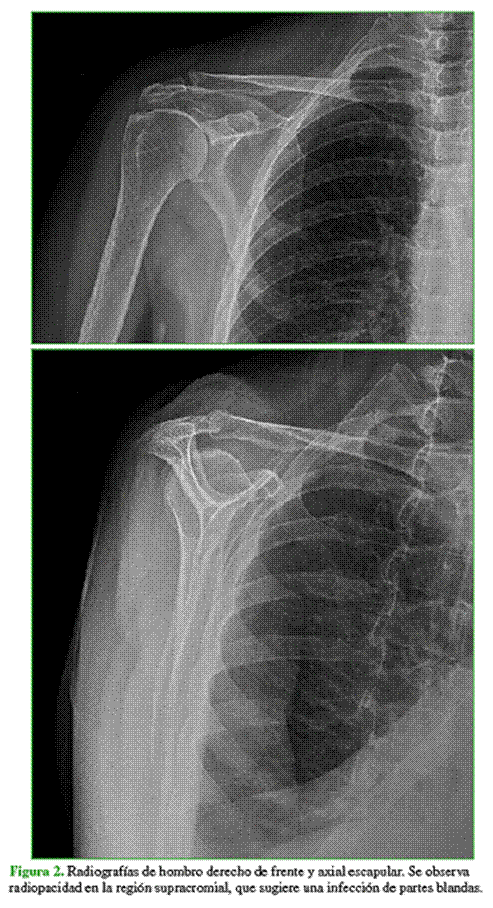

Solicitamos radiografías de hombro derecho de frente y axial escapular (Figura 2), en las que se observó radiopacidad en la región supracromial, y también una resonancia magnética que reveló irregularidades en las superficies articulares tanto del acromion como de la clavícula, asociadas a pequeñas colecciones circundantes y edema de partes blandas adyacentes (Figura 3).